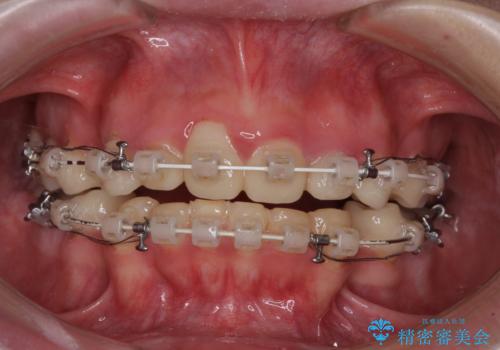

当初はほとんどの歯をむし歯治療のようにオールセラミッククラウンにて補綴治療を行う予定でしたが、仮歯に置き換えた時点で、口元の突出感や下顎前歯の叢生が気になるとのことで、上下左右の第一小臼歯4本を抜歯したワイヤー装置での抜歯矯正を行うこととしました。

矯正治療終了後に、残った歯をオールセラミッククラウンにて補綴治療を行うこととしました。